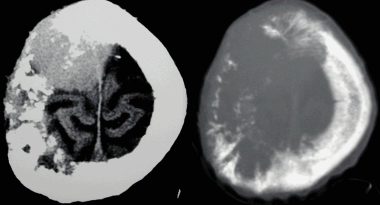

Метастазы головного мозга, фото. На КТ с контрастным усилением у пожилой пациентки (в верхнем ряду слева) с жалобами на головные боли выявлены множественные объемные образования в левом полушарии мозга, интенсивно накапливающие контрастное вещество. Образования имеют характерную форму в виде «кольца». На изображениях в нижнем ряду и вверху справа определяются множественные очаги в головном мозге: отчетливо видны округлые образования с более плотным «ободком» по периферии, располагающиеся в левой теменной доле.